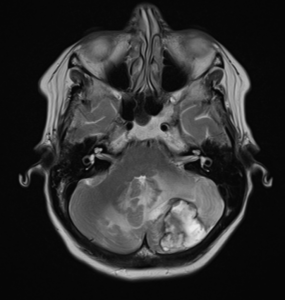

RM AXIAL T2